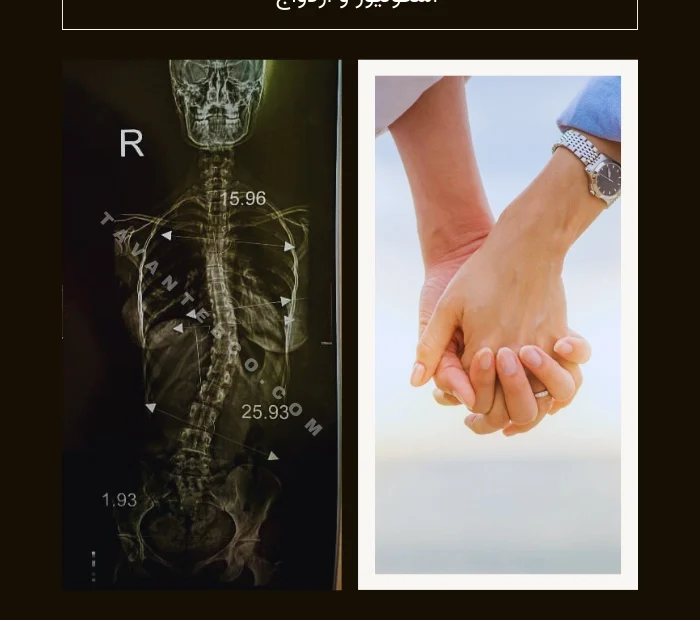

- 5 عکس پای سالم + عکس رادیولوژی پای سالم